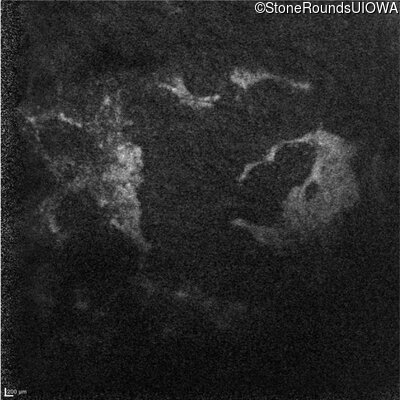

Age at visit: 38 years

This 38 year old woman had normal vision until age 22 when she noticed poor night vision when working as a camp counselor after college. Her hearing loss was first noticed at age 3 and was correctable with hearing aids.

Diagnosis & molecular findings

Usher Syndrome TUBB4B Arg262Gln CGG>CAG   AD